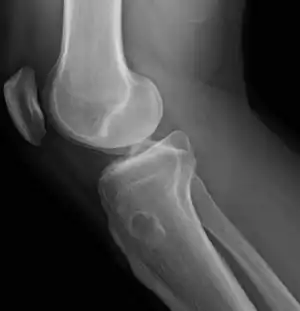

| Chondroblastoma[2] | ![]() | |